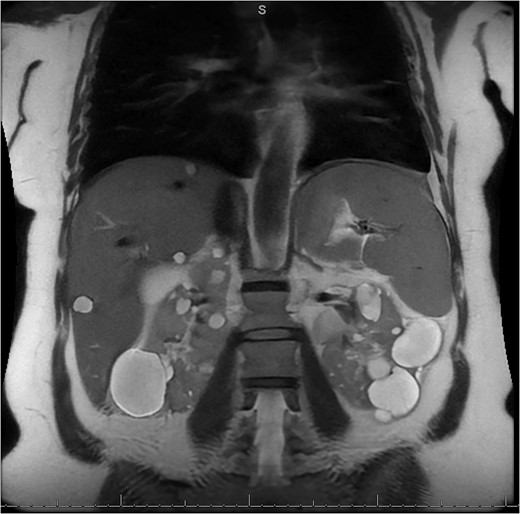

A 49-year-old female with a history of ADPKD and multiple liver cysts, 13-months status post subtotal cholecystectomy, endoscopic retrograde cholangiopancreatography with biliary sphincterotomy and balloon stone extraction, presented to the emergency department with fever and a 4-day history of discomfort in the right upper quadrant. At the time of the initial cholecystectomy, total cholecystectomy could not be performed due to extensive adhesions, and subtotal cholecystectomy with complete evacuation of the stones was done instead. Magnetic resonance cholangiopancreatography (MRCP) done at that time showed a dilated common bile duct (CBD) to 1.5 cm, intra and extrahepatic biliary dilatation, multiple liver cysts measuring up to 2 cm, and multiple stones in the CBD, including at the level of the ampulla (Fig. 1). Computerized tomography scan at the time of the second admission showed acute cholecystitis and she had mildly elevated transaminases, but there was no evidence of cholestasis or pancreatitis. MRCP showed minor proximal intrahepatic biliary dilation and cholelithiasis but no duct calculi (Figs 2–4). A laparoscopic cholecystectomy was attempted with extensive adhesiolysis between the gallbladder and surrounding omentum and mesocolon, but the cystic duct could not be isolated, and ultimately the cased was converted to open. While removing the gallbladder in a top-down fashion, a small bile leak was identified right at the closed end of the gallbladder remnant, where the bile duct was adhered to the gallbladder wall. Intraoperative cholangiogram was obtained through a small perforation in a right posterior bile duct at the site of attachment, which showed right posterior, right anterior and left hepatic ducts of equal size converged at a trifurcation (Fig. 5). The duct was repaired over a T-tube and observed throughout the rest of the case and no bile leak was identified. The gallbladder was opened along its lateral edge, revealing a hugely dilated cystic duct with ~10 to 12 marble-sized stones packed within the gallbladder remnant and cystic duct down to the juncture with the common bile duct. All the stones were removed and the safe portion of the gallbladder remnant was resected leaving the side attached to the bile duct in situ due to the Mirizzi anatomical variant. The cystic duct was oversewn along with the remnant of the gallbladder wall. Pathology showed acute-on-chronic cholecystitis with cholelithiasis. Repeat MRCP showed no retained stones in the biliary tree. The recovery course was unremarkable.

MRI/MRCP from second hospitalization demonstrating liver and kidney cysts.